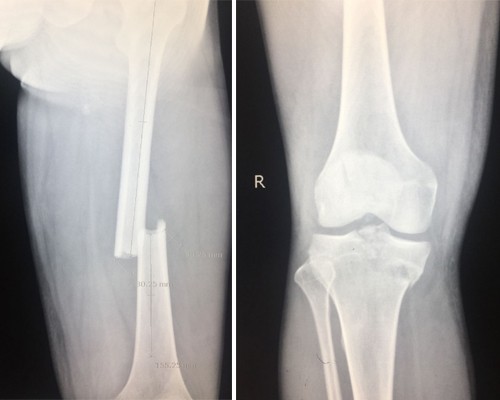

检查拍片显示:右股骨中段骨折、右胫骨上段粉碎性骨折、右髌骨粉碎性骨折、右侧眼眶内侧壁骨折。

术前.jpg

在宜宾民心创伤骨科医院骨科主任的带领下,团队迅速制定方案,完善术前检查,第一时间对患者进行了右股骨、胫骨上段、髌骨粉碎性骨折切开复位内固定手术治疗。